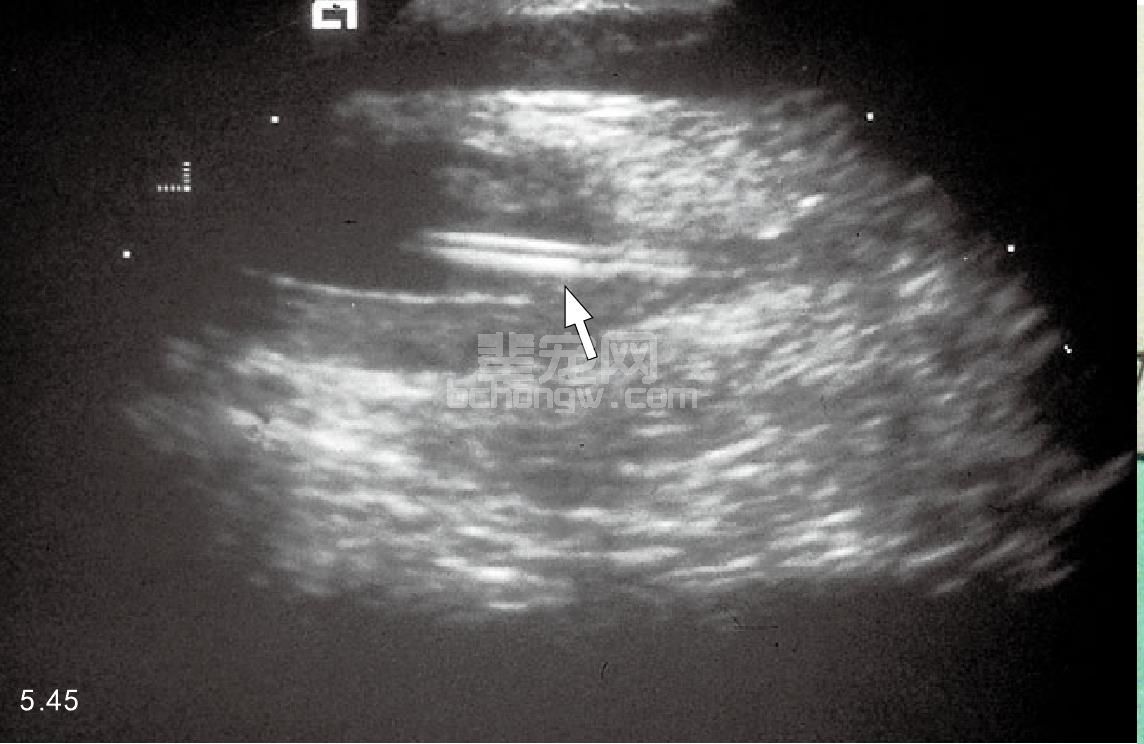

图5.45 超声检查猫的下泌尿道疾病,有一断裂的导尿管在膀胱内(箭头 所指)。诊断前导尿管在消除阻塞后用了将近2年。